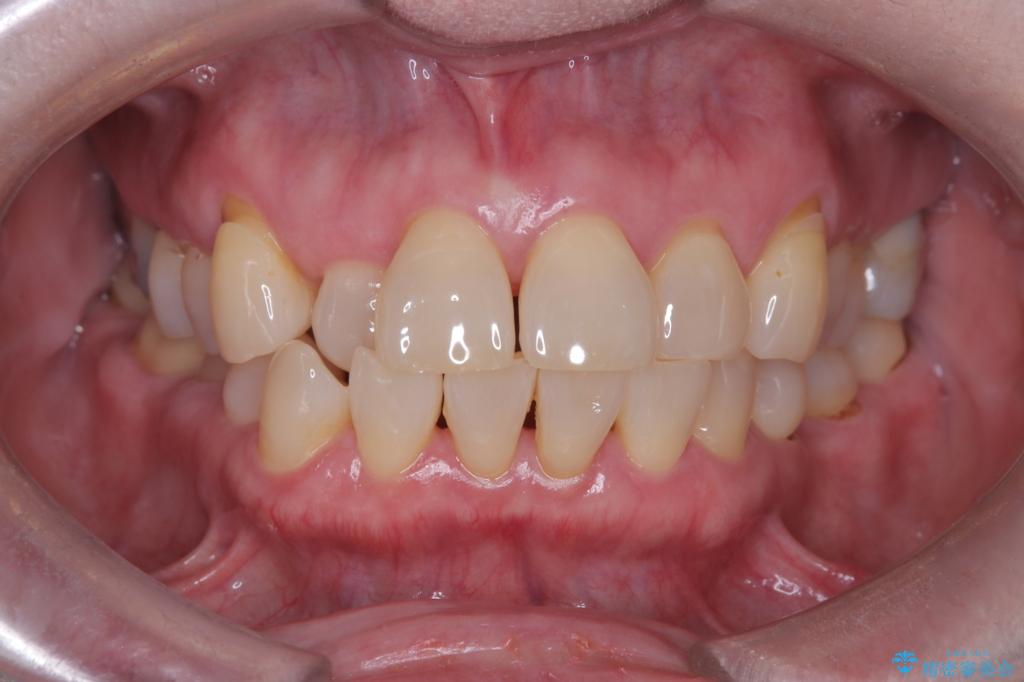

- 前歯の隙間とへこみが気になり、特に舌で触ると気になってストレスを感じるとのことで来院された患者様です。

上下ともに軽度の叢生があり、下顎がやや前突傾向にあったため、本来であれば矯正治療が第一選択となります。矯正によって下の前歯を後方に移動させることで、咬み合わせの改善とともに前歯のデコボコも整えることができます。

上下に叢生(歯のデコボコ)と反対咬合があるため、本来であれば矯正治療が最も理想的な治療選択となります。